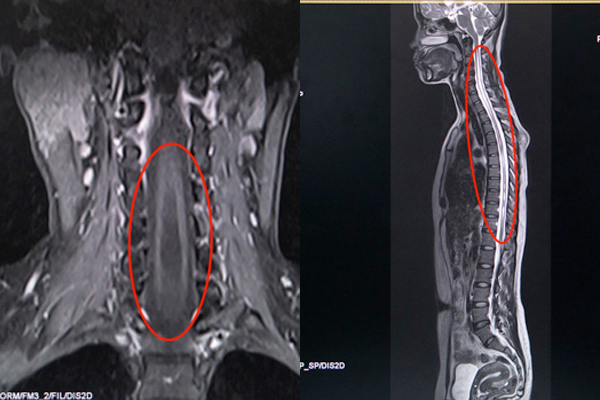

Bác sĩ chỉ định làm thêm cộng hưởng từ (MRI), phát hiện cột sống từ cổ gáy đến giữa lưng hình thành các hốc rỗng chứa đầy dịch tủy. Đây là biểu hiện đặc trưng của căn bệnh rỗng tủy (Syringomyelia) - một bệnh mạn tính hiếm gặp ở tủy sống với tỉ lệ 8,4/100.000 người, tập trung ở độ tuổi 20-50.

Hình ảnh chụp MRI cột sống của chị H. không phát hiện tủy sống một đoạn dài

Để phát hiện căn bệnh rỗng tủy, chụp MRI cột sống và tủy sống là công cụ đáng tin cậy trong chẩn đoán. Trong một số trường hợp, bác sĩ chuyên khoa sẽ tiêm chất cản giúp phân biệt hình ảnh của khối u hay các bất thường khác.